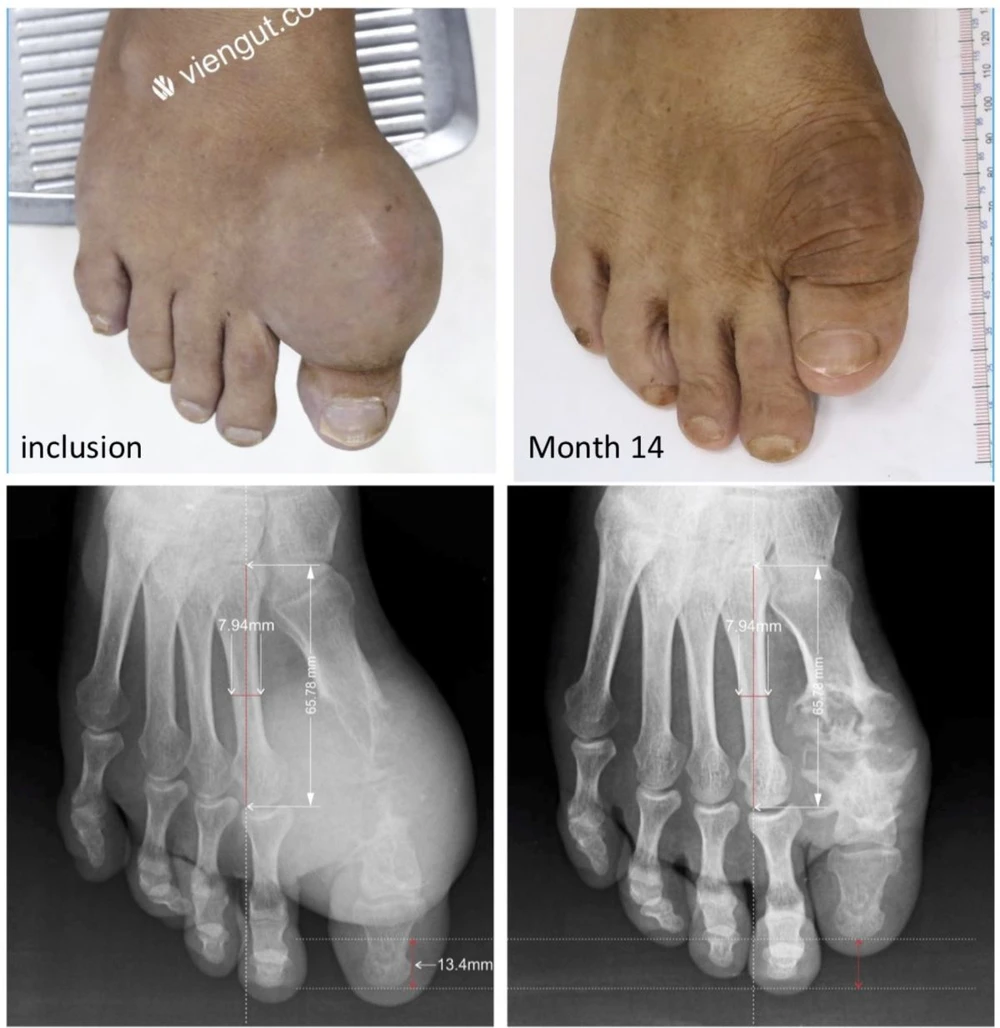

Kết quả điều trị tan hết tinh thể urat, tiêu hết u cục tophi của Viện Gút cho những bệnh nhân gút bị biến chứng nặng đã được công bố tại Hội nghị thường niên Hội thấp khớp học Mỹ (ACR) năm 2020.

Hình ảnh điều trị tan tophi của Viện Gút được công bố tại Hội nghị thường niên Hội Thấp khợp học Mỹ (ACR) 2020.png

Hình ảnh điều trị tan tophi của Viện Gút được công bố tại Hội nghị thường niên Hội Thấp khớp học Mỹ (ACR) 2020.

Từ năm 2017 đến nay, Viện Gút TP.HCM đã giúp cho hàng ngàn bệnh nhân gút từ chưa bị biến chứng đến biến chứng nặng, được điều trị tan tinh thể urat lắng đọng. Nhiều bệnh nhân đã tan hết tinh thể urat lắng đọng, hết tái phát viêm đau khớp gút cấp, hết tiêu chuẩn chẩn đoán bệnh gút, được chữa khỏi bệnh gút theo hướng dẫn của EULAR.